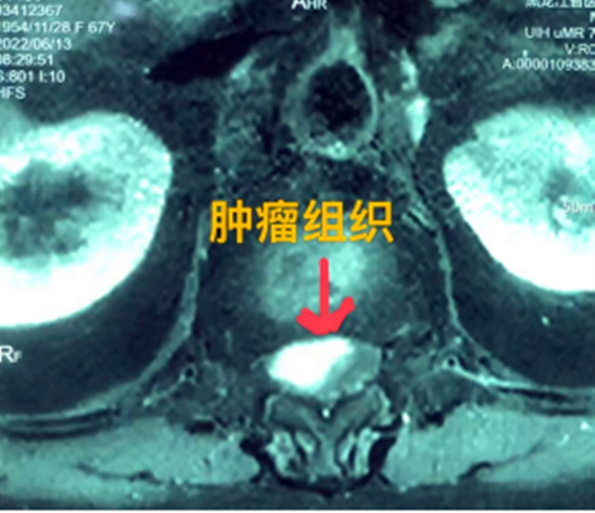

據(jù)省醫(yī)院神經(jīng)外一科陶宇醫(yī)生介紹,家住外地的張大娘最近總感覺(jué)雙下肢疼痛、無(wú)力,且排尿困難及便秘,伴有行走困難。時(shí)間長(zhǎng)了,張大娘病情逐漸加重,劇烈的疼痛甚至讓她無(wú)法完整入睡。在當(dāng)?shù)蒯t(yī)院,張大娘按腰椎肩盤(pán)突出接受治療,但未見(jiàn)好轉(zhuǎn),隨后進(jìn)行的胸椎MRI(核磁共振)檢查,結(jié)果不禁讓張大娘和家屬瞠目結(jié)舌,原來(lái)張大娘患的竟然是少見(jiàn)的脊髓腫瘤。

張大娘住進(jìn)了黑龍江省醫(yī)院神經(jīng)外一科,該科孫國(guó)章主任醫(yī)師熱情地接待了張大娘,并邀請(qǐng)骨外一科專(zhuān)家共同為她進(jìn)行了聯(lián)合會(huì)診。發(fā)現(xiàn)張大娘病情十分復(fù)雜棘手,脊髓腫瘤體積較大,充滿髓腔且神經(jīng)已經(jīng)完全受壓,需要手術(shù)來(lái)完整切除。同時(shí)還發(fā)現(xiàn)張大娘的胸腰部曾受過(guò)兩次外傷,伴有多處骨折,這對(duì)接下來(lái)的手術(shù)操作帶來(lái)一定影響。